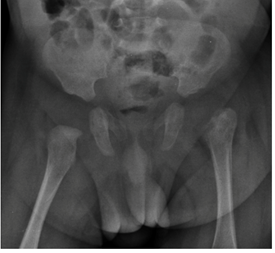

En la evolución, previo al alta médica, se observó clínicamente una dismetría de los miembros inferiores, con una prueba de Galeazzi positiva. Por lo cual se realiza una ecografía de ambas caderas que muestra una alteración de las relaciones articulares a izquierda, y una radiografía de pelvis en la cual se evidencia una luxación de la misma, así como una reacción perióstica en la metáfisis del fémur (Figura 4), la cual se interpreta como una complicación de una osteoartritis séptica, y que dado el diagnóstico tardío y buena evolucion del paciente se decide realizar control evolutivo de la misma.

Figura 4: Radiografía AP de pelvis en la cual se evidencia una luxación de la misma, así como una reacción perióstica en la metáfisis del fémur